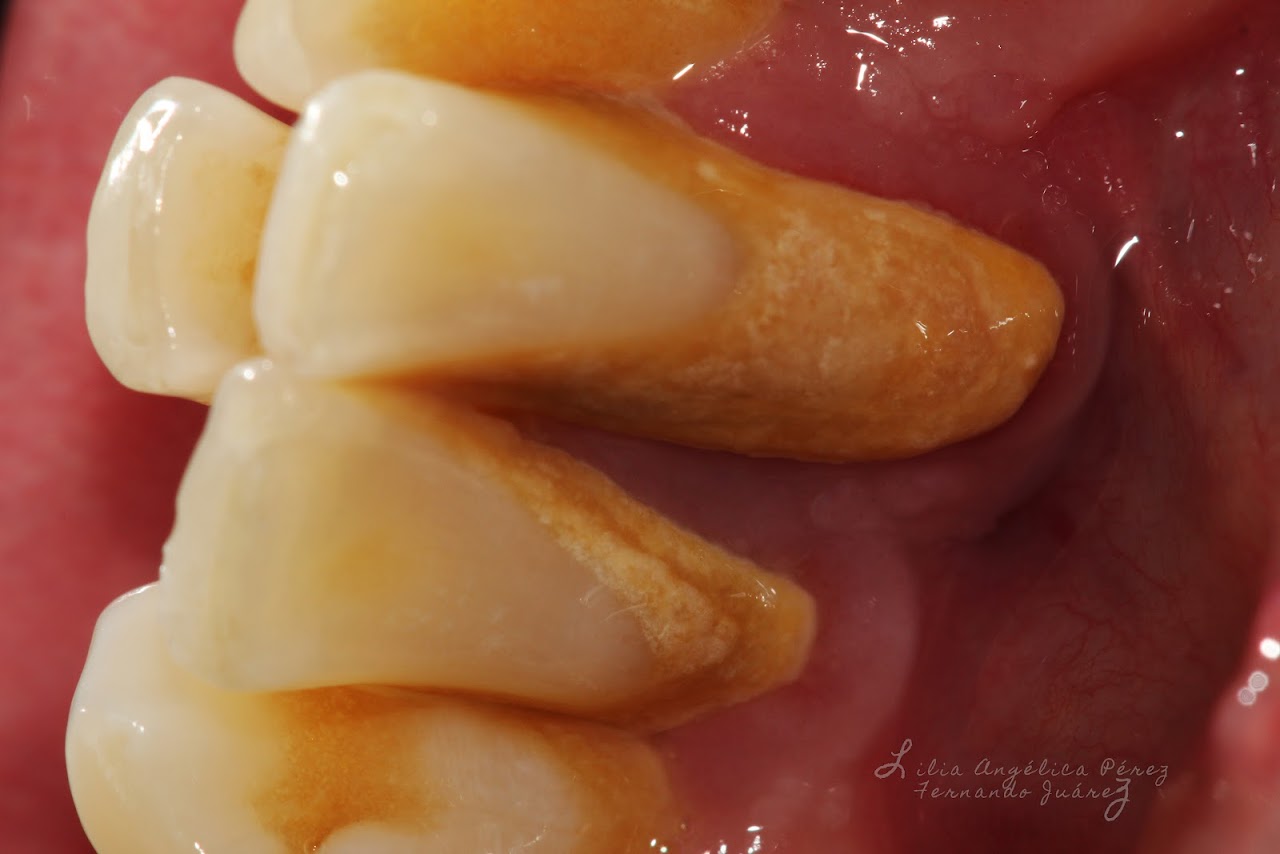

Sarro dental en incisivos

Sarro dental: aspecto y localización frecuente en cuello de dientes.